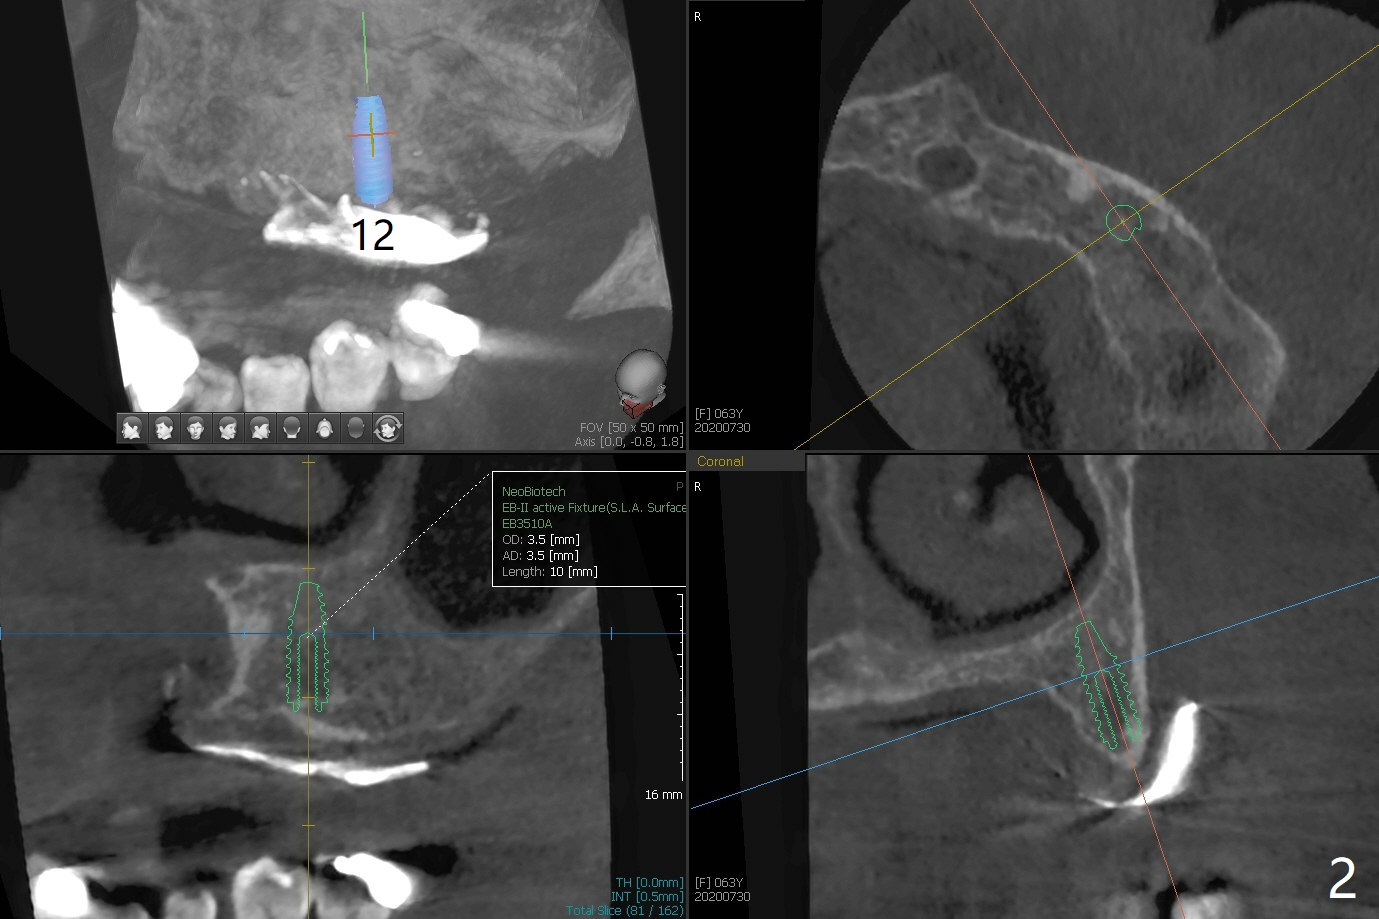

A 63-year-old woman presents to clinic with fractured crown/post at #26 (Fig.1). After recementation of the crown, the upper Valplast RPD is found to be unstable. After discussion, she agrees to have two implants and ball abutments at #11 and 13 for retention. Use pink acrylic to fixate a denture tooth of #3 to the Valplast. Alginate impression (upper and lower jaws with RPDs and upper without RPD) will be taken to make radiographic stent (Barium Sulfate). With the latter, take small field CT (5x5 cm) to decide the size of the implants. After implant and ball abutment placement, soft reline the Valplast until osteointegration. When Barium Sulfate and Jet are mixed with monomer, the mixture is applied to tissue surface of #11-13 of the upper Valplast. CT is taken. The latter shows that the bone at #11 is thin, while the bone at #14 is short. The sites of #12 and 13 are proper for implant placement (Fig.2,3).